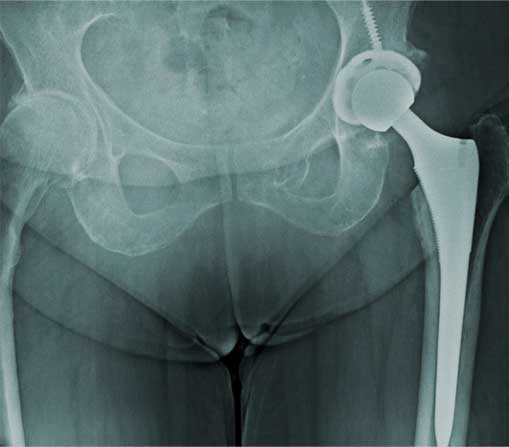

Prótesis de cadera

Es también conocida como reemplazo de cadera, la cual consiste en la sustitución de la articulación dañada o un implante de metal, cerámica o plástico que realiza la función de la articulación, mejorando el dolor.

Las indicaciones más comunes son la artrosis o desgaste de cadera en adultos mayores, otras indicaciones son las fracturas de cadera, el daño crónico o infección, artritis reumatoide, secuelas de enfermedades de la cadera o traumatismos, las cuales se presentan en adultos jóvenes y adultos mayores.